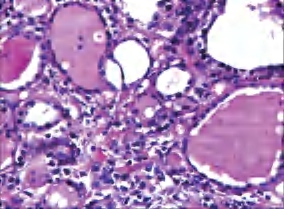

2.镜下 甲状腺部分滤泡破坏,溢出的胶质周围有组织细胞和多核巨细胞包绕,形成肉芽肿,但无干酪样坏死。间质可见多量嗜酸性粒细胞、淋巴细胞和浆细胞浸润。愈合期表现为滤泡上皮再生、间质纤维化及瘢痕形成(图3-27、图3-28)。

图3-28 亚急性肉芽肿性甲状腺炎,残留胶质周围有多核巨细胞围绕、炎细胞浸润形成的肉芽肿